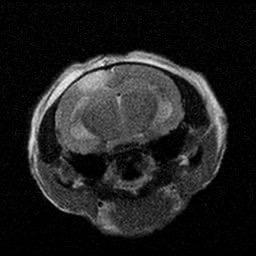

Figure 2. (A-B) Representative MRI images showcasing the lesioned brain area ofChrdl1 Ckoand Cre(-)mice at1daypost-stroke and 7days post-stroke. (C) Bar graph comparison of stroke volume between Cre (-) andCkomice,1dayand7dayspoststroke.Statisticaldifferencesbetween groups or time points, where applicable, are indicated by asterisks (*p< 0.05, **p<0.01). (D) Line graph comparison of stroke area percentage betweenCre(-)andCkomice,1dayand7dayspoststroke.